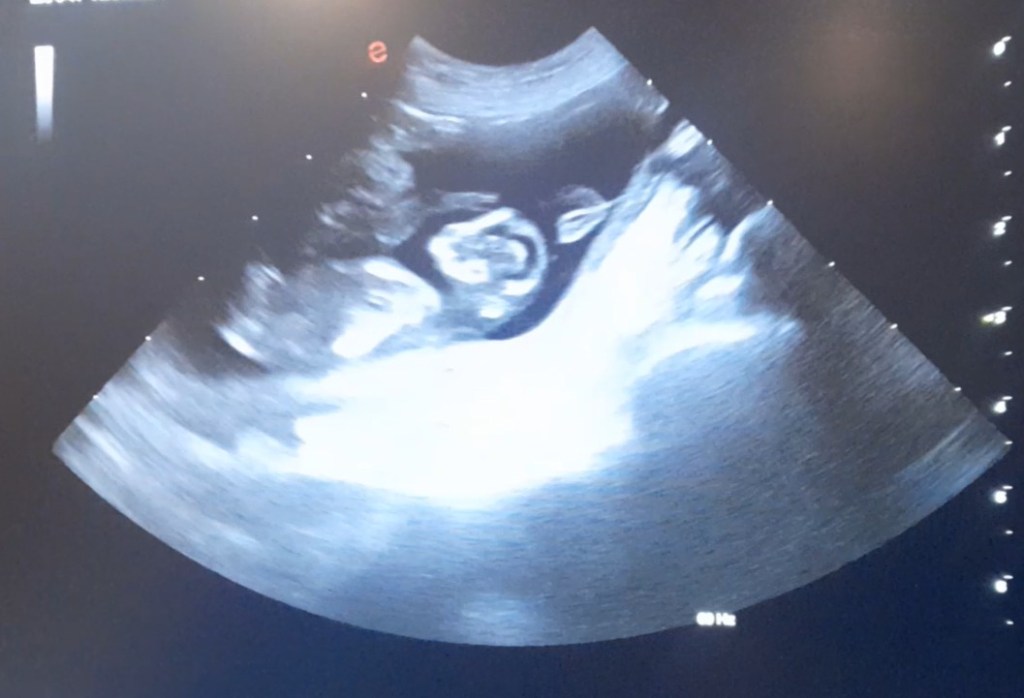

Het is gelukt, Elke en Loutje krijgen pups, de echo is gemaakt, er zijn er genoeg te zien!!!